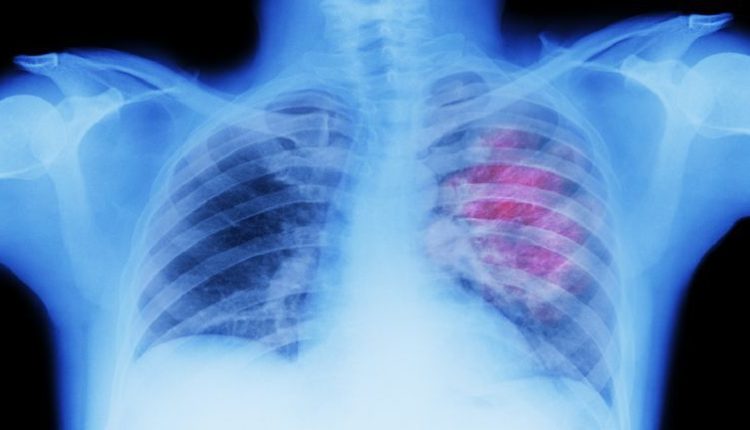

ولفت الاستشاري إلى أن أخطر المراحل هي التي تحدث بعد التعرض للغاز بتركيز عالٍ أو لفترة طويلة نسبياً: “الضرر الأكبر يكمن في إمكانية حدوث الوذمة الرئوية (الاستسقاء الرئوي)، حيث تتجمع السوائل في الرئتين. هذا يمنع تبادل الأكسجين بشكل فعال، وقد يؤدي إلى تدمير جزئي أو كلي للقصبات الهوائية والأسناخ، الأمر الذي يضع المصاب في خطر الفشل التنفسي ويهدد حياته على الفور”.

* طلب الرعاية الطبية: “يجب نقل جميع المصابين، حتى أولئك الذين تبدو أعراضهم خفيفة، إلى المستشفى. الوذمة الرئوية قد تتأخر في الظهور لساعات، ولهذا يجب وضعهم تحت المراقبة المكثفة للحصول على دعم الأكسجين وتقييم الرئتين عبر الفحوصات المتخصصة”.